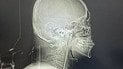

Российские оккупанты 16 апреля атаковали Запорожье беспилотниками, попав в остановку общественного транспорта и повредив восемь окрестных многоэтажек. По данным главы ОВА Ивана Федорова, в результате удара пострадал двухлетний мальчик, который находится под наблюдением медиков.